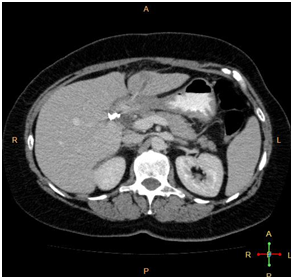

A 50year old woman presented to our hospital with a 4week history of dyspepsia and vague abdominal pain with exacerbation of symptoms and vomiting in the last 2weeks prior to presentation. Her abdomen was soft and non tender on examination. Computerised tomography (CT) scan of the abdomen demonstrated mural thickening at the anterior wall of the duodenum and associated fat stranding. This was seen in association with an obliquely oriented hyperdense focus extending from the gastric lumen across the first part of the duodenum into segment 3 of adjacent liver with surrounding poorly defined irregular hypodensity measuring 21x15x16mm in size, suspicious for liver abscess (Figure 1).

Figure 1